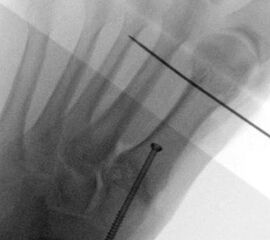

Operationstechnik

Abbildung 2

Abbildung 3

Abbildung 4